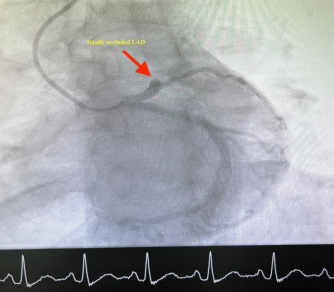

Coronary angiography showed a large caliber ectatic left anterior descending (LAD) artery, which was occluded by thrombus (Figure 1). Despite difficulties in wiring the LAD, the involved segment was successfully ballooned in an escalated fashion, restoring TIMI-3 flow. An ectatic segment that is just distal to the involved segment was also noted, which was studded with thrombus, resulting in a very hazy picture (Figure 2). Although attempts were made to aspirate the thrombus using an Export catheter (Medtronic, MN, USA), it was unsuccessful. Since the patient was symptomatically and hemodynamically stable, a decision was then made to medically manage him for the next 24-48 hours before attempting the procedure again.

Figure 1: Diagnostic angiogram showing a complete occlusion of LAD.